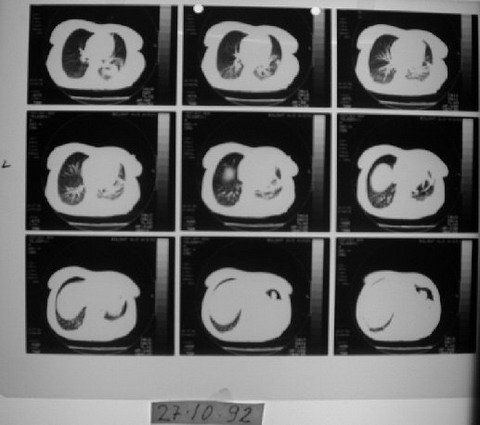

VAKA RAPORU- Teşhis: Maliyn lenfoma, akciğer kanseri - MG

EK MG3

27 Ekim 1992'de çekilen bilgisayarlı tomografi ve değerlendirme raporu.